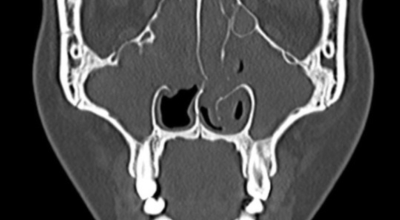

얼굴의 뼛속에는 몇 개의 빈 공간이 있어요. 이런 빈 공간을 '코 옆에 있는 동굴들'이라고 하는 의미에서 부비동이라 합니다. 이 공간은 머리 뼛속에 있는 뇌를 외부의 충격으로부터 보호해 주는 역할을 합니다. 부비동염은 이런 부비동이라는 빈 공간에 세균, 바이러스가 침투해서 염증이 발생한 질환을 의미합니다. 부비동염은 흔히 '축농증'이라고 불려요.

부비동염은 증상과 기간에 따라 '급성 부비동염'과 '만성 부비동염'으로 구분돼요. 부비동 코 주위의 얼굴 뼛속에 있는 빈 공간은 숨 쉬는 공기의 온도와 습도를 조절하며, 외부의 충격으로부터 뇌를 보호합니다. 부비동은 작은 구멍을 통해 콧속과 연결되어요. 이를 통해 콧속이 환기되고 부비동 내의 분비물이 자연스럽게 콧속으로 배출됩니다. 부비동염은 이 부비동에 염증이 발생해서 콧물이 배출되지 못하고 고여 있는 상태를 말합니다.